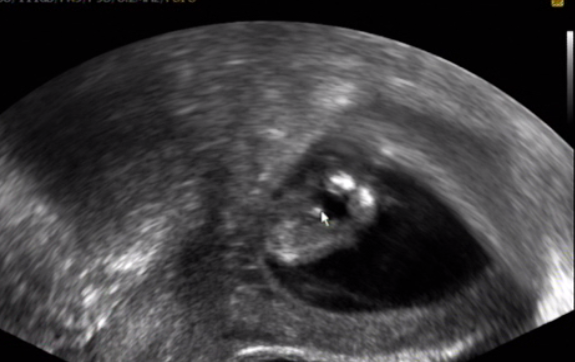

[883491]ja tam teda nevidim vubec nic,ani samotne mimi zda tam teda je vubec zabrane cele

[883496] nee to je jen kousííček právě s pindííkem nejspíše :D mám natočené video tak jsem to pauzla a udělala print screen :)